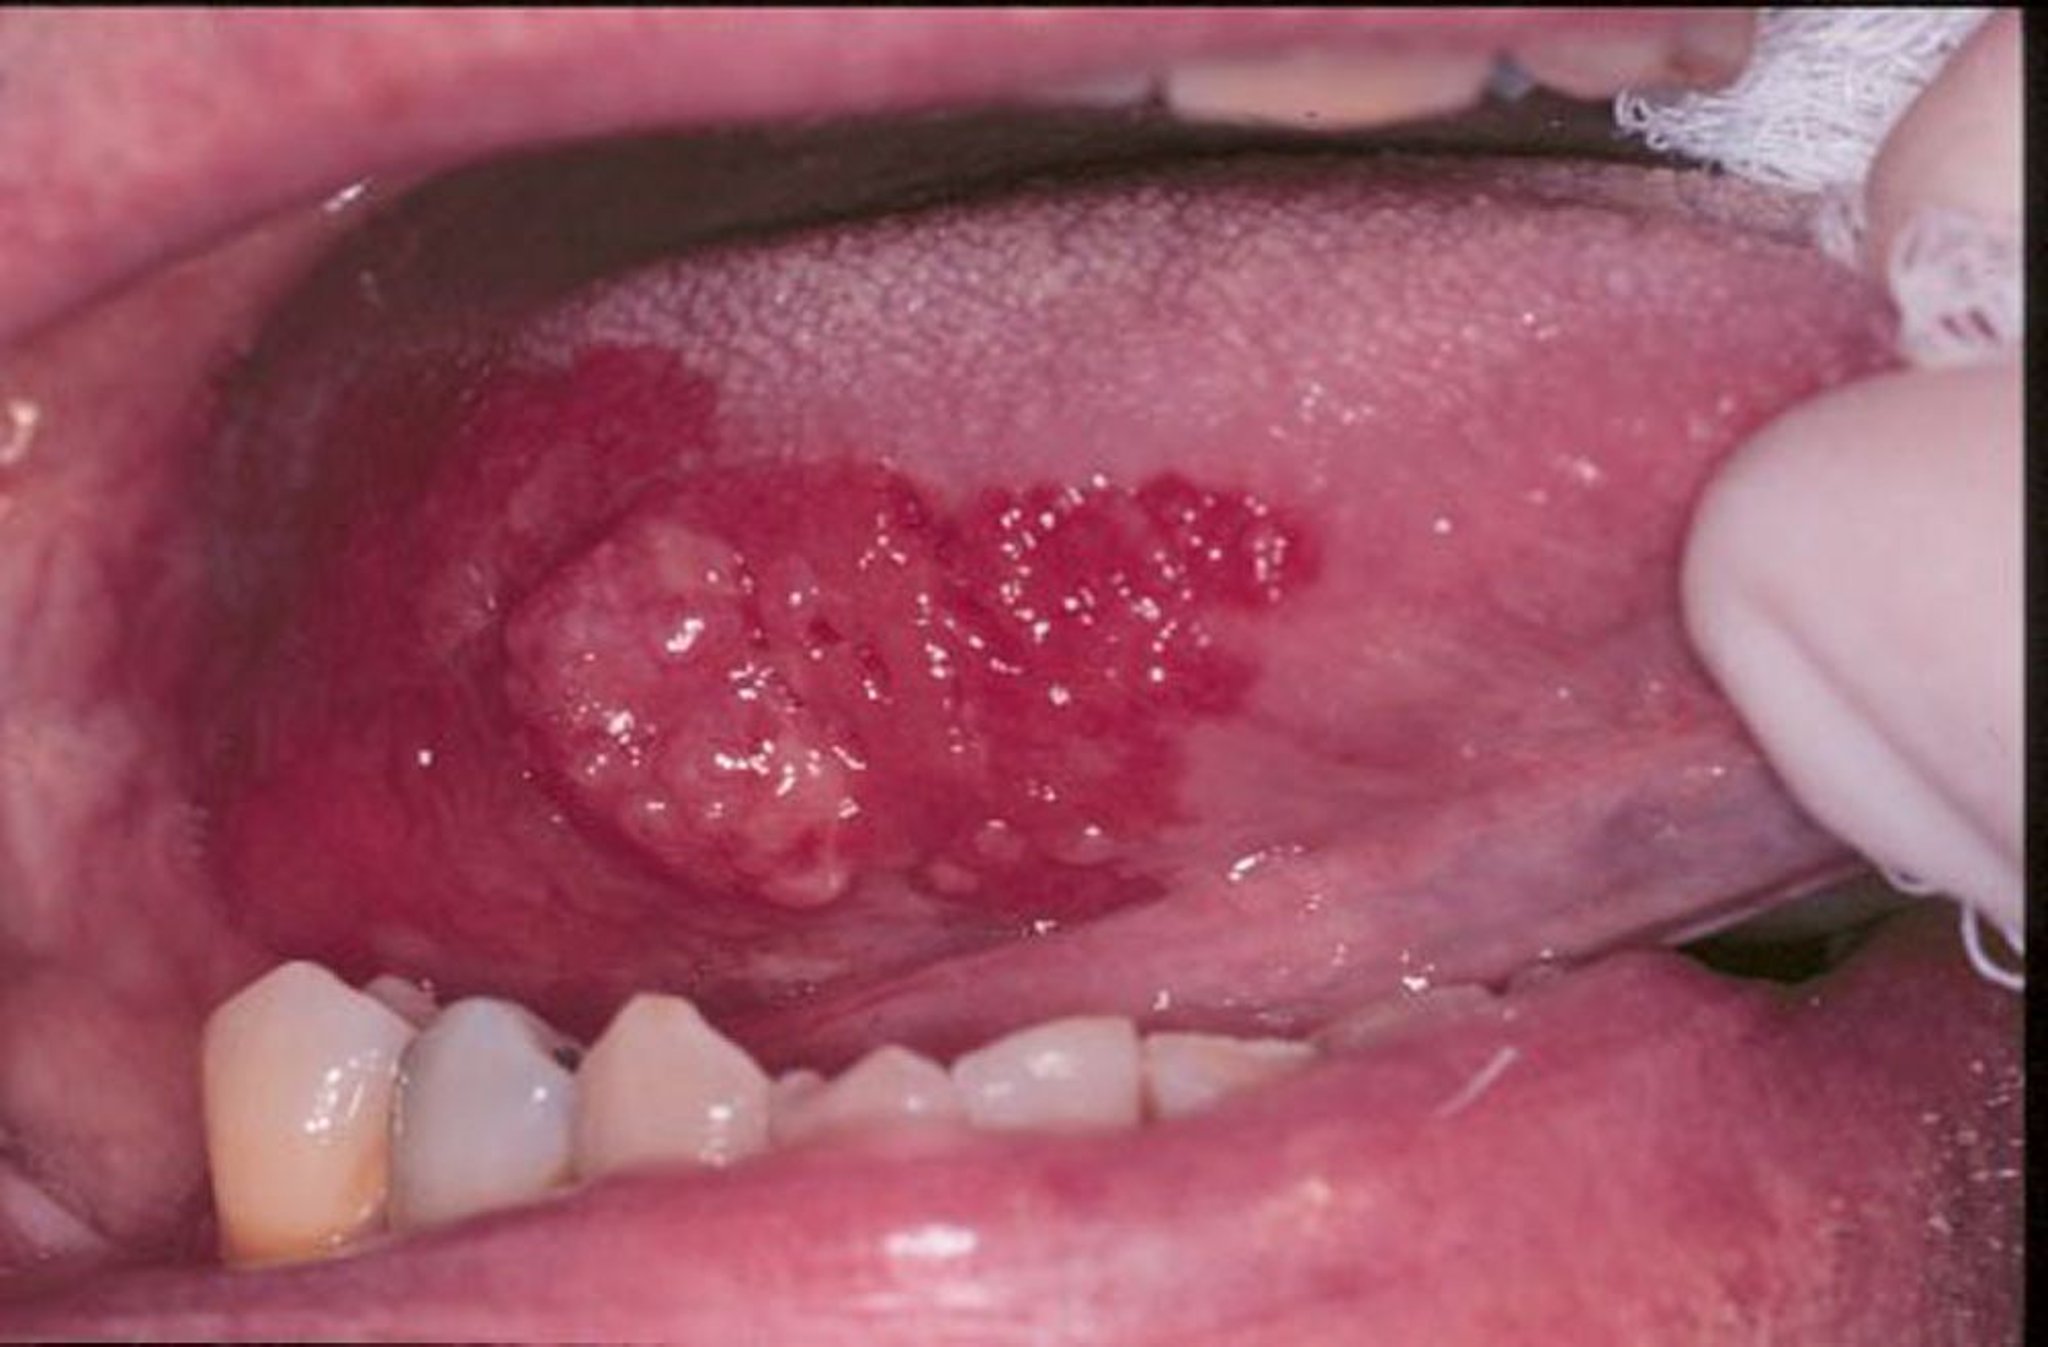

홍색판은 입에 나타나는 빨갛고 편평하거나 또는 닳아진 벨벳처럼 보이는 상처들을 총칭하는 말입니다. 이 사진에서 편평 세포 암종은 홍색판에 의해 주변이 둘러 쌓여 있습니다.

이미지 제공: Jonathan A. Ship, DMD.